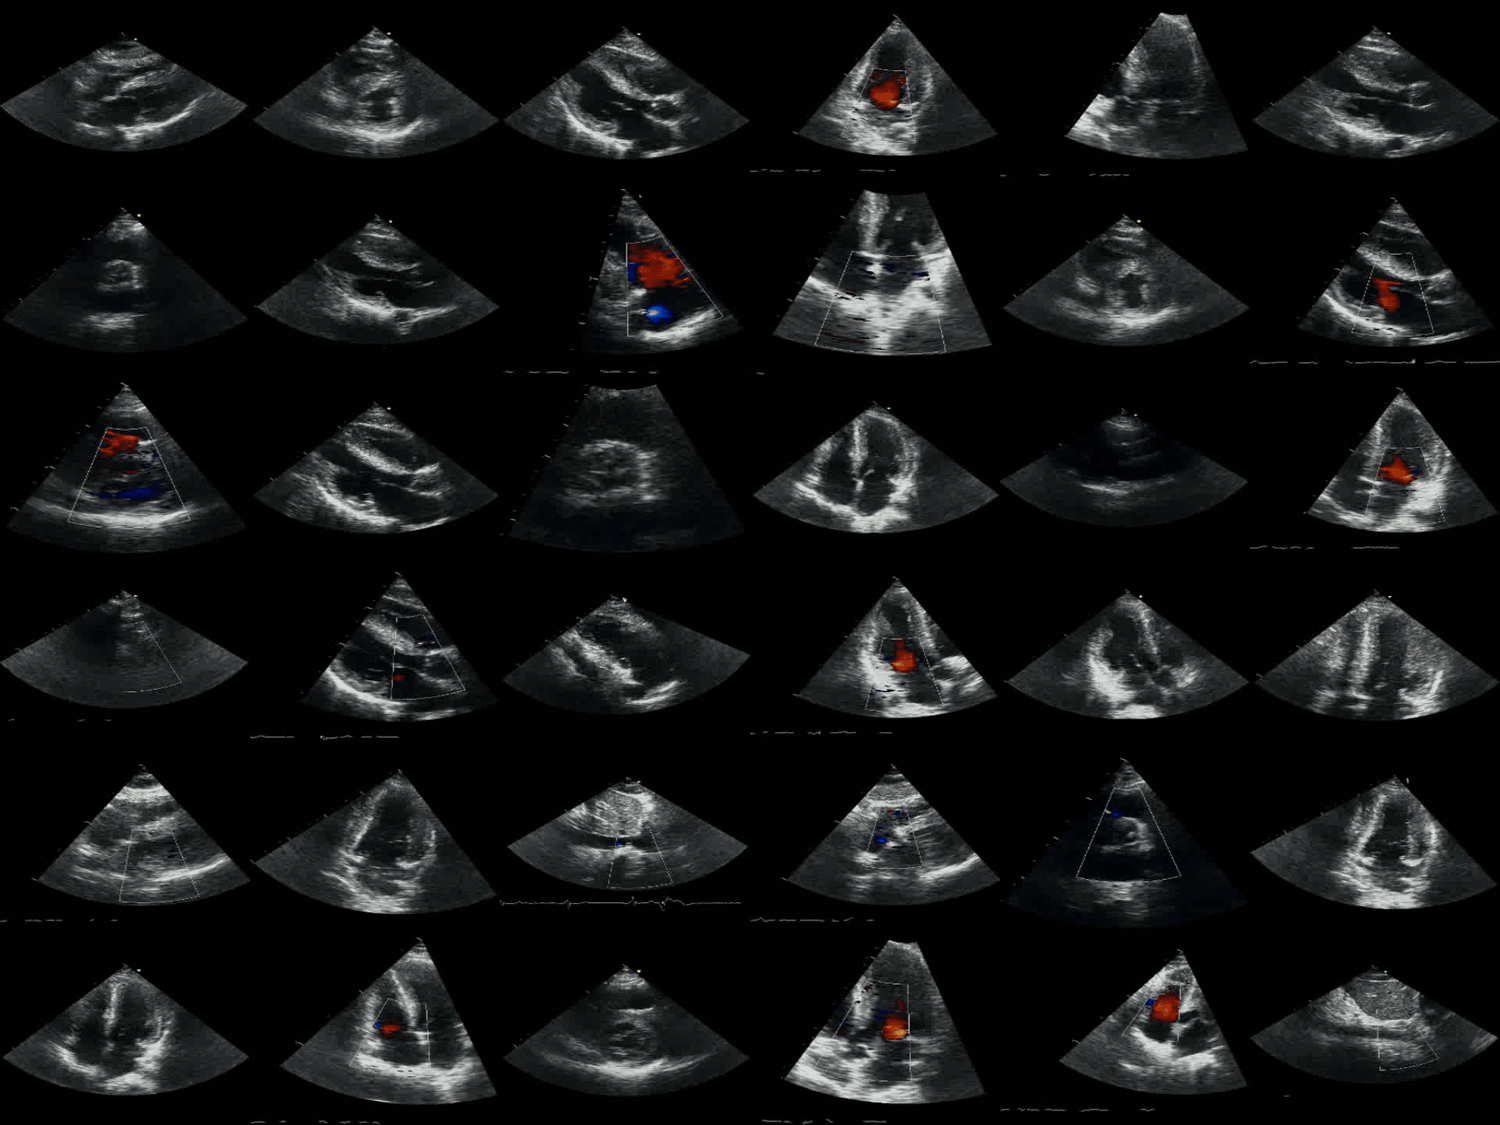

A single echocardiogram study consists of many distinct image and video views of the heart

Set of echo views

We applied the multi-view neural network architecture to several demonstration tasks in cardiac ultrasound, also called echocardiography. Echocardiography is the most common cardiovascular imaging modality and its interpretation regularly requires synthesis of complementary information across multiple views.

Each echocardiographic slice of the heart contains incomplete 2D information about the heart's 3D structure and function. By simultaneously accepting multiple views as input and integrating information across them, the multi-view neural network derives a more complete understanding of cardiac anatomy and function.

Image courtesy of Atif Qasim MD; www.echocardiographer.org